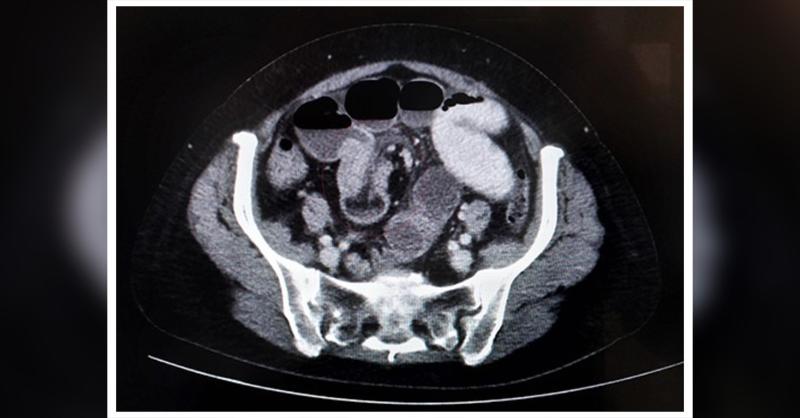

- Ileo-Ileal Intussusception in a 60-year-Old Female

The invagination of a proximal portion of the intestine (intussusceptum) into an adjacent distal segment (intussuscipiens) like a telescope, is known as intussusception. (1) Approximately 1% of cases of adult bowel obstruction can result in intussusception, and about >90% have a distinct underlying cause associated with bowel. (2) Inflammatory fibr